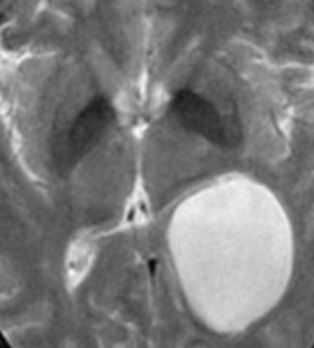

Дольчатые образования, которые заполняют, расширяют ликворные пространства, оказывают постепенно нарастающий масс-эффект, проникают между структурами и охватывают соседние нервы и сосуды. Частой особенностью кист задней черепной ямки является смещение основной артерии в сторону от моста.

Сочетание клеточных остатков вместе с высоким содержанием холестерина понижают плотность эпидермоидов приблизительно до 0 HU; таким образом, эпидермоидные кисты могут быть идентичными по плотности с ликвором, и выглядеть так же, как арахноидальные кисты.

Кальцификация не часто (10-25% случаев); редко эпидермоидная киста может быть гиперденсной вследствие кровотечения, омыления или высокого содержания белка ("белые эпидермоиды").

Они не копят контраст, и только в очень редких случаях демонстрируют накопление контраста стенкой.

Проявления на МРТ схожи с таковыми на КТ; эпидермоиды часто неотличимы от арахноидальных кист или расширенных ликворных пространств на многих последовательностях.

- обычно изоинтенсивны ликвору (65%)

- редко гипоинтенсивные, как правило , в случаях так называемых "белых эпидермоидов"

- обычно неоднородный / "грязный" сигнал; выше, чем от ликвора